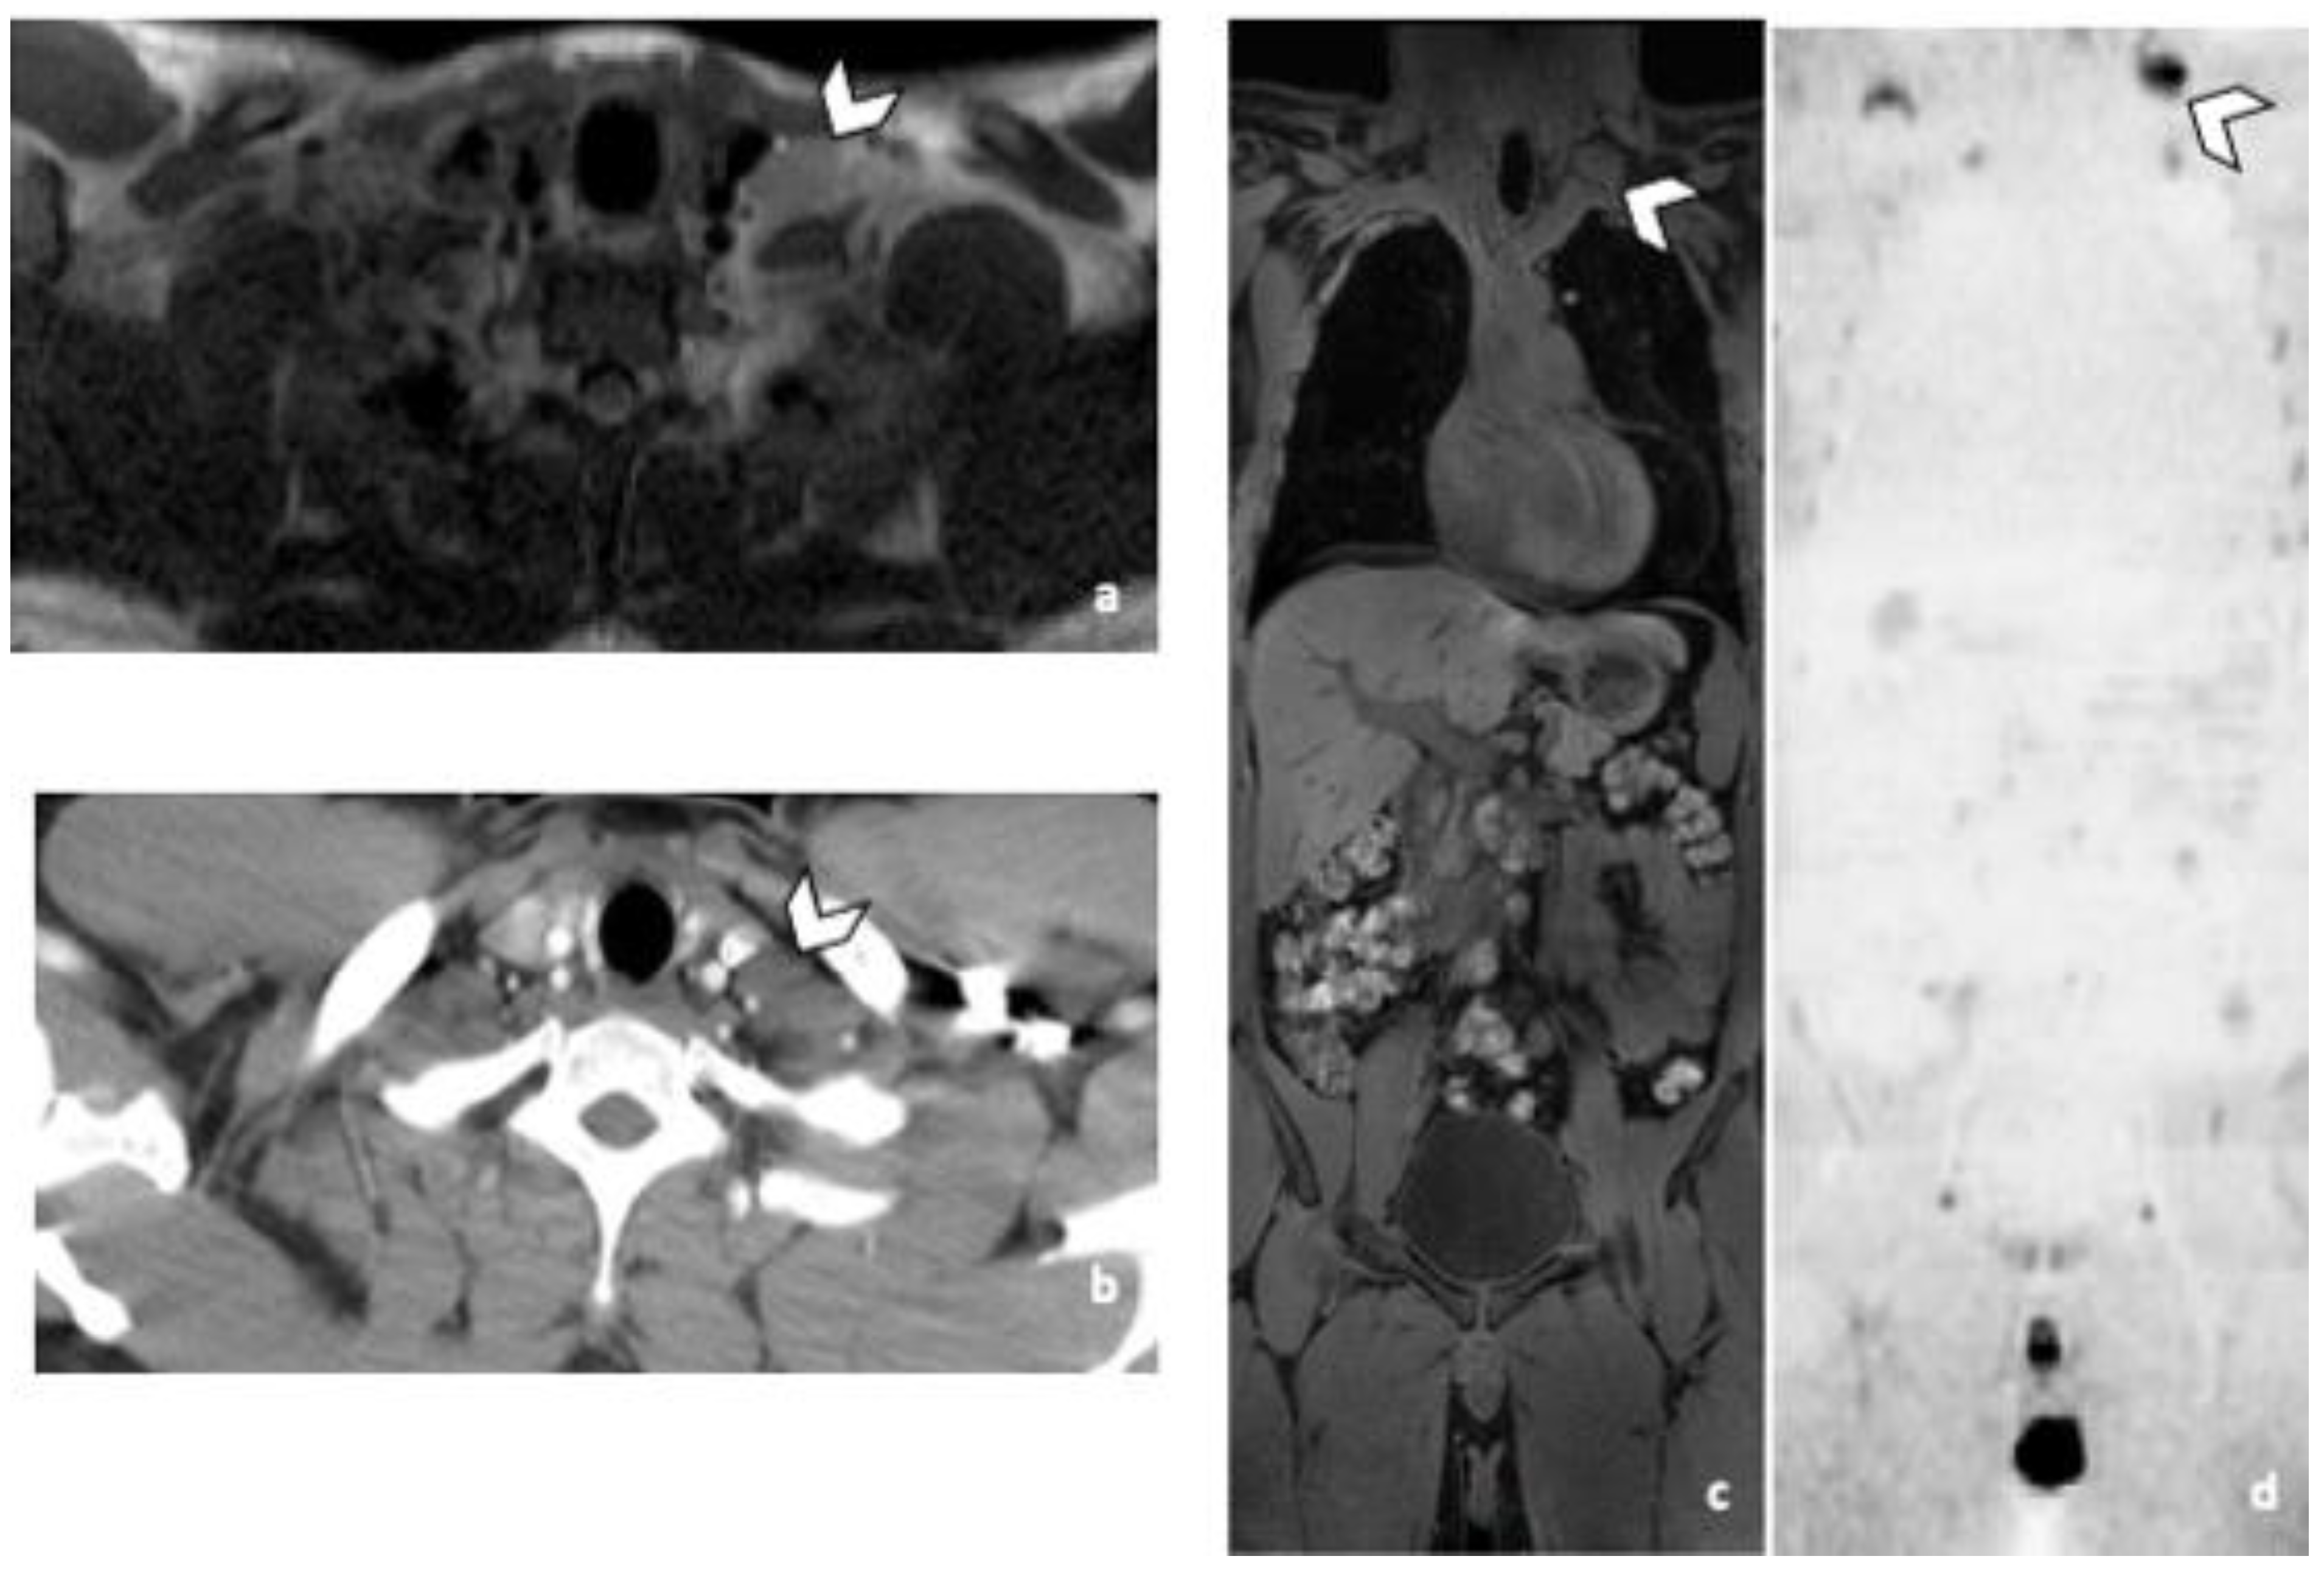

Practically with the sole use of CT, 2 and 3 patients with supradiaphragmatic LN would have been missed depending on the reader. R1 missed 3 supra-diaphragmatic DLN and R2 two during CT readings. Both readers missed one patient, because of the non-contrast CT due to allergy contraindication. The second patient missed by both readers, had a left supraclavicular LN in the limit of the field of view of the CT (Figure 3). Its detection was difficult because of its inherent contrast. The inherent contrast is the extent to which the attenuation coefficient value of a structure differs from the one of the surrounding tissues [16]. In this case the attenuation values of the LN and the surrounding muscles are similar, the contrast is low and the lesions are not easily distinguishable. Another reason could be the arm raised position. The third DLN patient missed by one of the two readers during the CT readings, had a paraoesophageal LN, better visualized in MRI and DWI sequence (Figure 4). For R2 the specificity of both techniques was 97% for DLN because a thymic cyst was misinterpreted as a necrotic LN.

Figure 3.

False negative supra-diaphragmatic lymph node during the CT reading in a 28-year-old man with NSGCC. Axial T2-weighted image (a), coronal reformatted 3D T1 GRE Fat Sat (c) and high b-value DWI (inverted greyscale, b = 1000 s/mm2) MR images of the whole body (d) and axial CT image after intravenous injection of iodinated contrast agent (b). The enlarged left supra-clavicular lymph node (arrowhead) was identified by both readers during the MRI readings; it was missed by both readers during the CT readings. Abbreviations: NSGCC: Non-Seminomatous Germ Cell Cancer, 3D: Three Dimensional, T1 GRE: T1 Gradient Echo, DWI: Diffusion Weighted Imaging, MRI: Magnetic Resonance Imaging, CT: Computed Tomography.